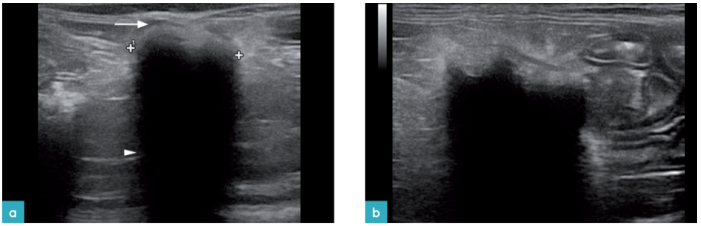

血栓会出现在主动脉或其分支或在后腔静脉里。猫最易发生动脉血栓(图26)。血栓在超声上的形态与它存在的时间有关。最初,无回声的血栓很难被发现。使用彩色多普勒,能量多普勒或频率多普勒可以发现管腔内的血栓(图27)。随着时间的推移,附壁血栓产生回声,在B模式上可见血管的充盈缺损。

发生髂内动脉远端血栓的患猫,通常是有心肌病伴有左心房扩张。肿瘤的侵袭,副肿瘤综合征,异物或原因不明也可引发血栓。

血栓通过左心室进入主动脉造成栓塞。当猫就诊时可能没有心血管方面的症状,只表现为后肢的麻痹。